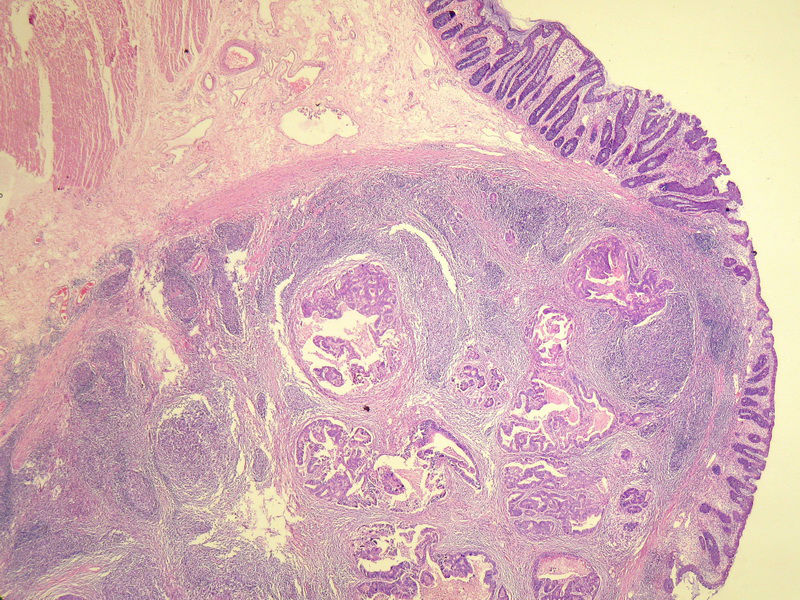

70岁男性,乙状结肠息肉样肿物。

请教:这个乙状结肠肿瘤侵犯到哪一层??图1

仅就浸润的深度而言,粘膜下层应该没什么争议。但是肿瘤表面的粘膜腺体是很好的,从低倍图看,不能排除是个转移灶的可能。请临床再查一查除了这个以外别的部位还有没有肿块。

浸润深度为粘膜下层,可粘膜表面的腺体完整,同意楼上的观点。谢谢